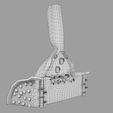

神经肌肉接头示意图